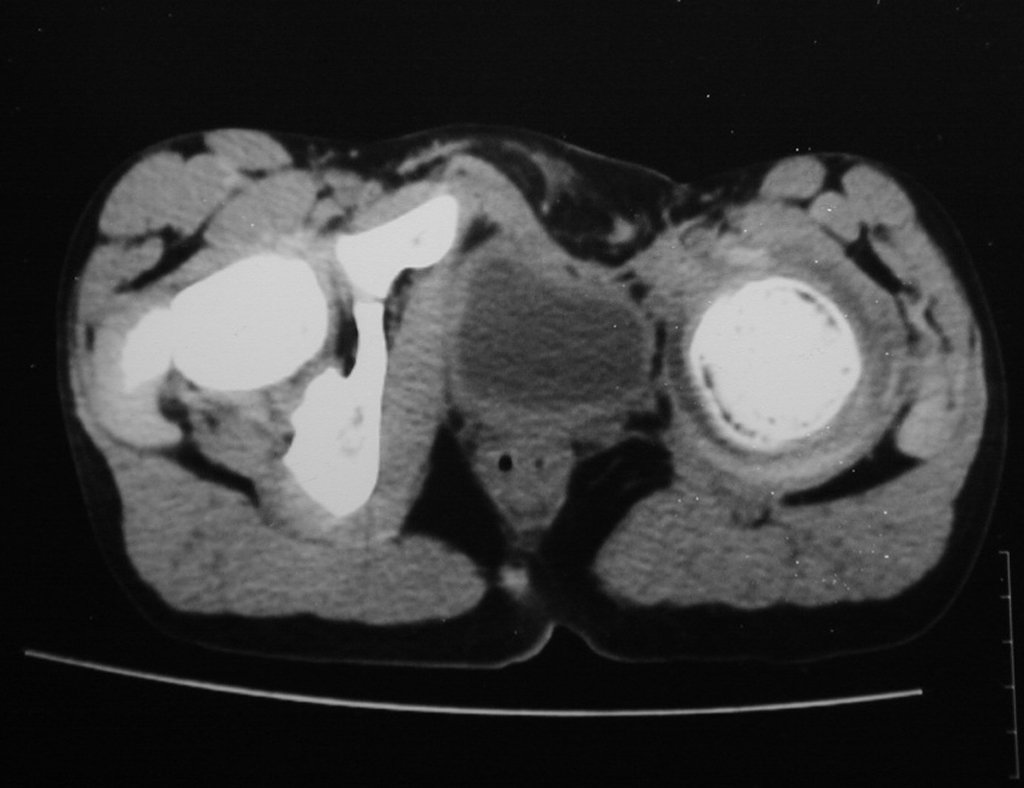

Foram realizados os exames para estadiamento sistêmico, que não demonstraram outro sítio de neoplasia (Figuras 5 à 7).